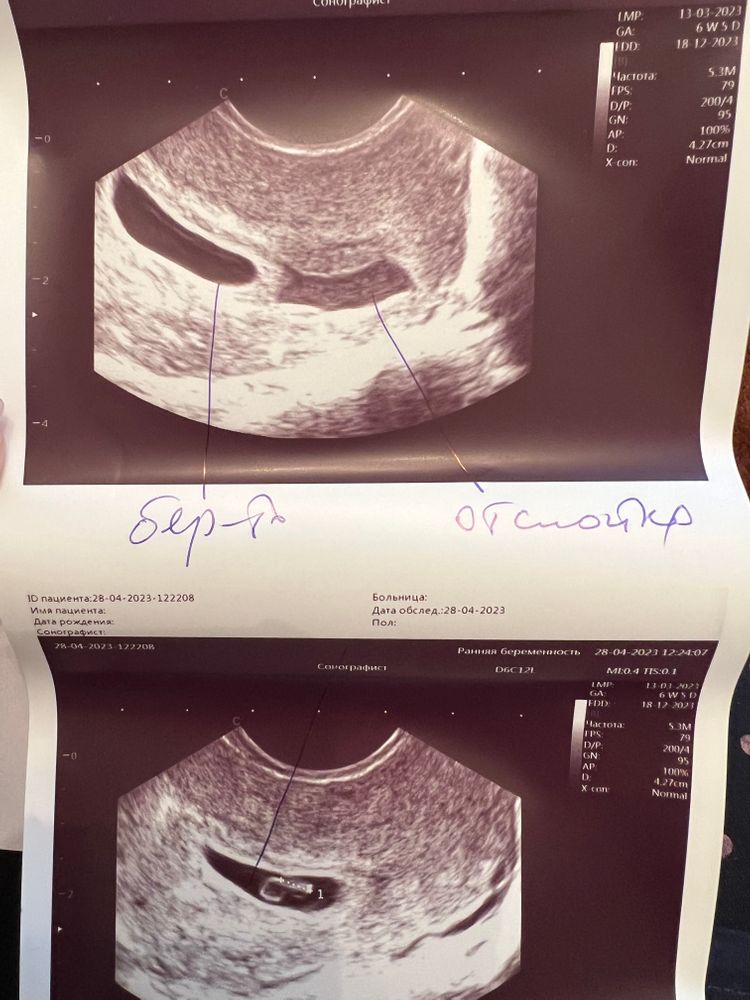

Беременность 6 недель.

Изображение Вот наше описание остаточной полости.

Скорее всего это остаточная полость а не отслойка

Постельный режим, отлежаться дома, если работаете -возьмите больничный, в большинстве сама рассасывается